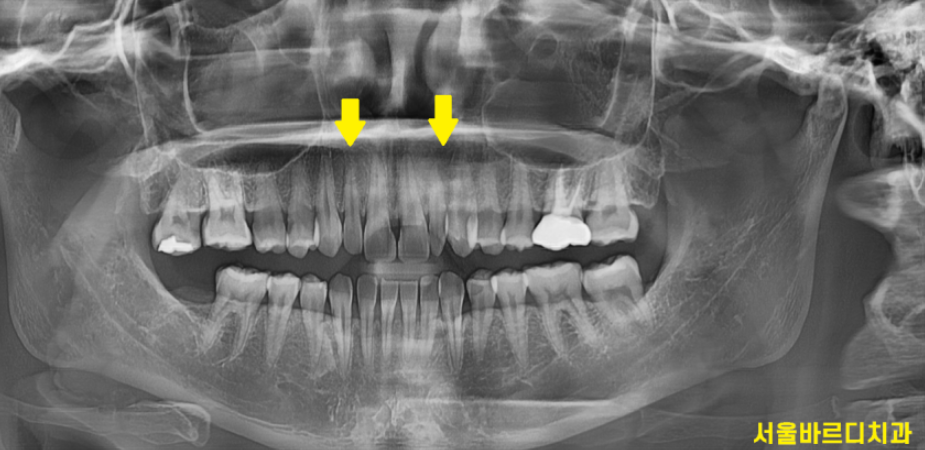

x-ray를 보니 송곳니 ,

맨 앞 대문니에 비해 크기가 작은게 눈에 보이실겁니다.

이러다보니 작은 치아 콤플렉스가 있으셨다고 합니다ㅠㅠ